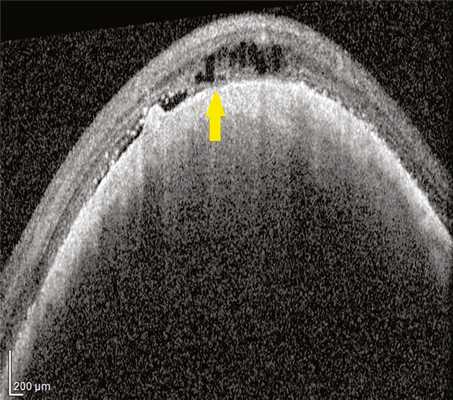

В 15 (22,4%) глазах визуализированы зоны разрыва МБ и РПЭ, нарушение дифференцировки структуры хориоидеи и сетчатки при средней проминенции МХ — 2,76±0,23 мм, среднем диаметре — 9,1±0,52. В этих глазах на ОКТ-сканограммах в зоне опухоли МБ была представлена в виде тонкой интенсивно гиперрефлективной линии на границе опухолевого комплекса и сетчатки. На протяжении этой линии имелись локальные дефекты с изменениями, аналогичными описанным выше (рис. 2). Рис. 2. Горизонтальный ОКТ-скан через МХ (проминенция 2,9 мм). Стрелкой указан локальный дефект МБ.